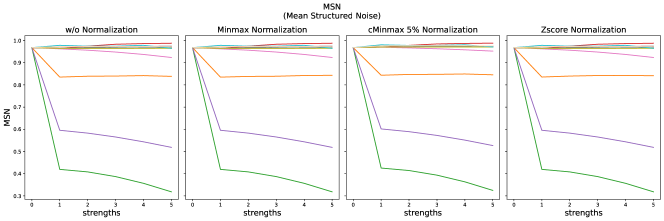

4.2 Non-Reference Metrics

The results for all strengths are given in Fig. A.5. For the maximum strength (s=5), the results are summarized in Tab. 9 without normalization and for cMinMax normalization.

Minmax normalization and Zscore normalization do not have any effect on the selected non-reference metrics, therefore these results are not shown here.

MSN decreased most strongly for stripe artifacts, Gaussian noise and ghosting. The difference for higher distortion strengths is only small, while the lowest distortions are already detected.

The MSN metrics represents the line-wise correlation between neighboring lines. The reference value in our experiments lies at 96%, which is probably caused by high anatomical consistency in the present pixel spacing. It strongly decreases for stripe artifacts, which fits to the fact, that the stripes change relations between local image intensities and are not oriented along the x- or y-axis. Random Gaussian noise, reduces statistical correlation and thereby also MSN. Ghosting also reduces MSN, as it additionally distorts image intensities locally.